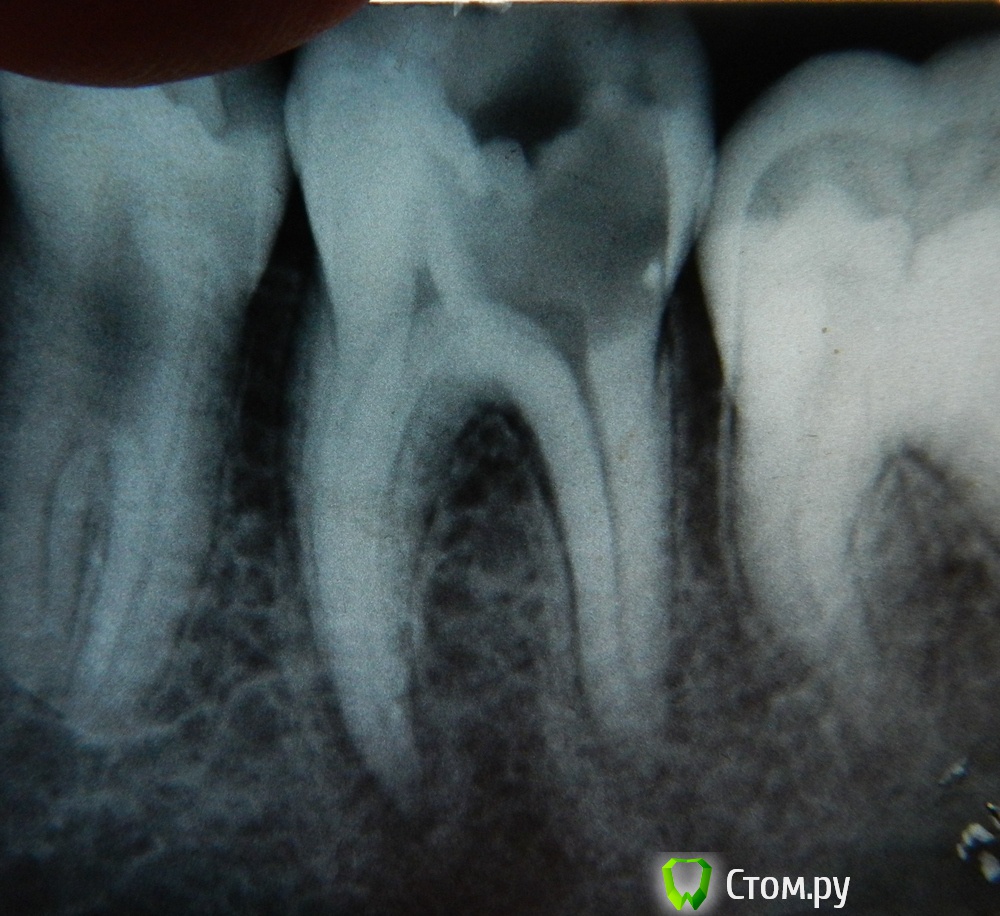

torshin Опубликовано 7 декабря, 2013 Поделиться Опубликовано 7 декабря, 2013 Здравствуйте! Мне 19 лет. После начала лечения 36-го зуба (препарирования его и удаления нервов) от него остались: стенка со стороны 5-го зуба и пол стенки со стороны щеки... Посоветуйте, пожалуйста, каким способом его лучше всего восстановить. Врач хочет ставить пломбу на стекловолоконном штифте с формированием зуба из пломбировочного материала. Коронку, говорит, делать пока не стоит. Хочется узнать ваше мнение. фотография рентгена трёхгодичной давности. К сожалению свежего рентгена у меня нет, но там всё то же только еще видно воспаление под расширенным каналом. Врач сказала, что чуть позже была бы гранулема. - временная пломба, отмечены оставшиеся стенки зуба. Ссылка на комментарий